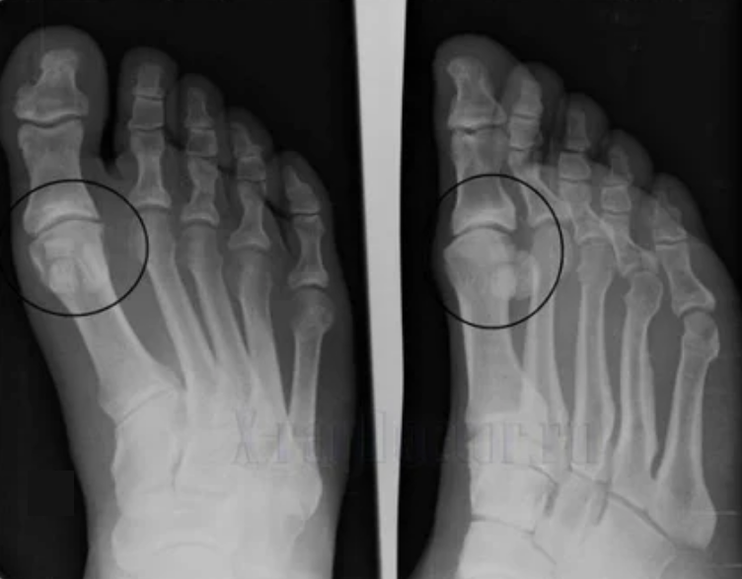

To make a diagnosis, rheumatologists study the patient's complaints and prescribe an X -ray exam. Most of the time, radiography is used in 2 projections.The doctor analyzes the presence of dystrophic disorders in hyaline cartilage and bone joints.If the joint gap is reduced, bones will be deformed or flat, there are cystic formations on the cartilage surface, osteophytes are obvious signs of arthrosis.During inspection, arthrosis indicates the instability of the joint: the limb axis and subluxation is disturbed.

Often an x -ray image is not able to provide complete information about the condition of the joint.For a more complete study, computed tomography is prescribed, effective for examining bones.Magnetic resonance imaging is most often used to study soft tissues.